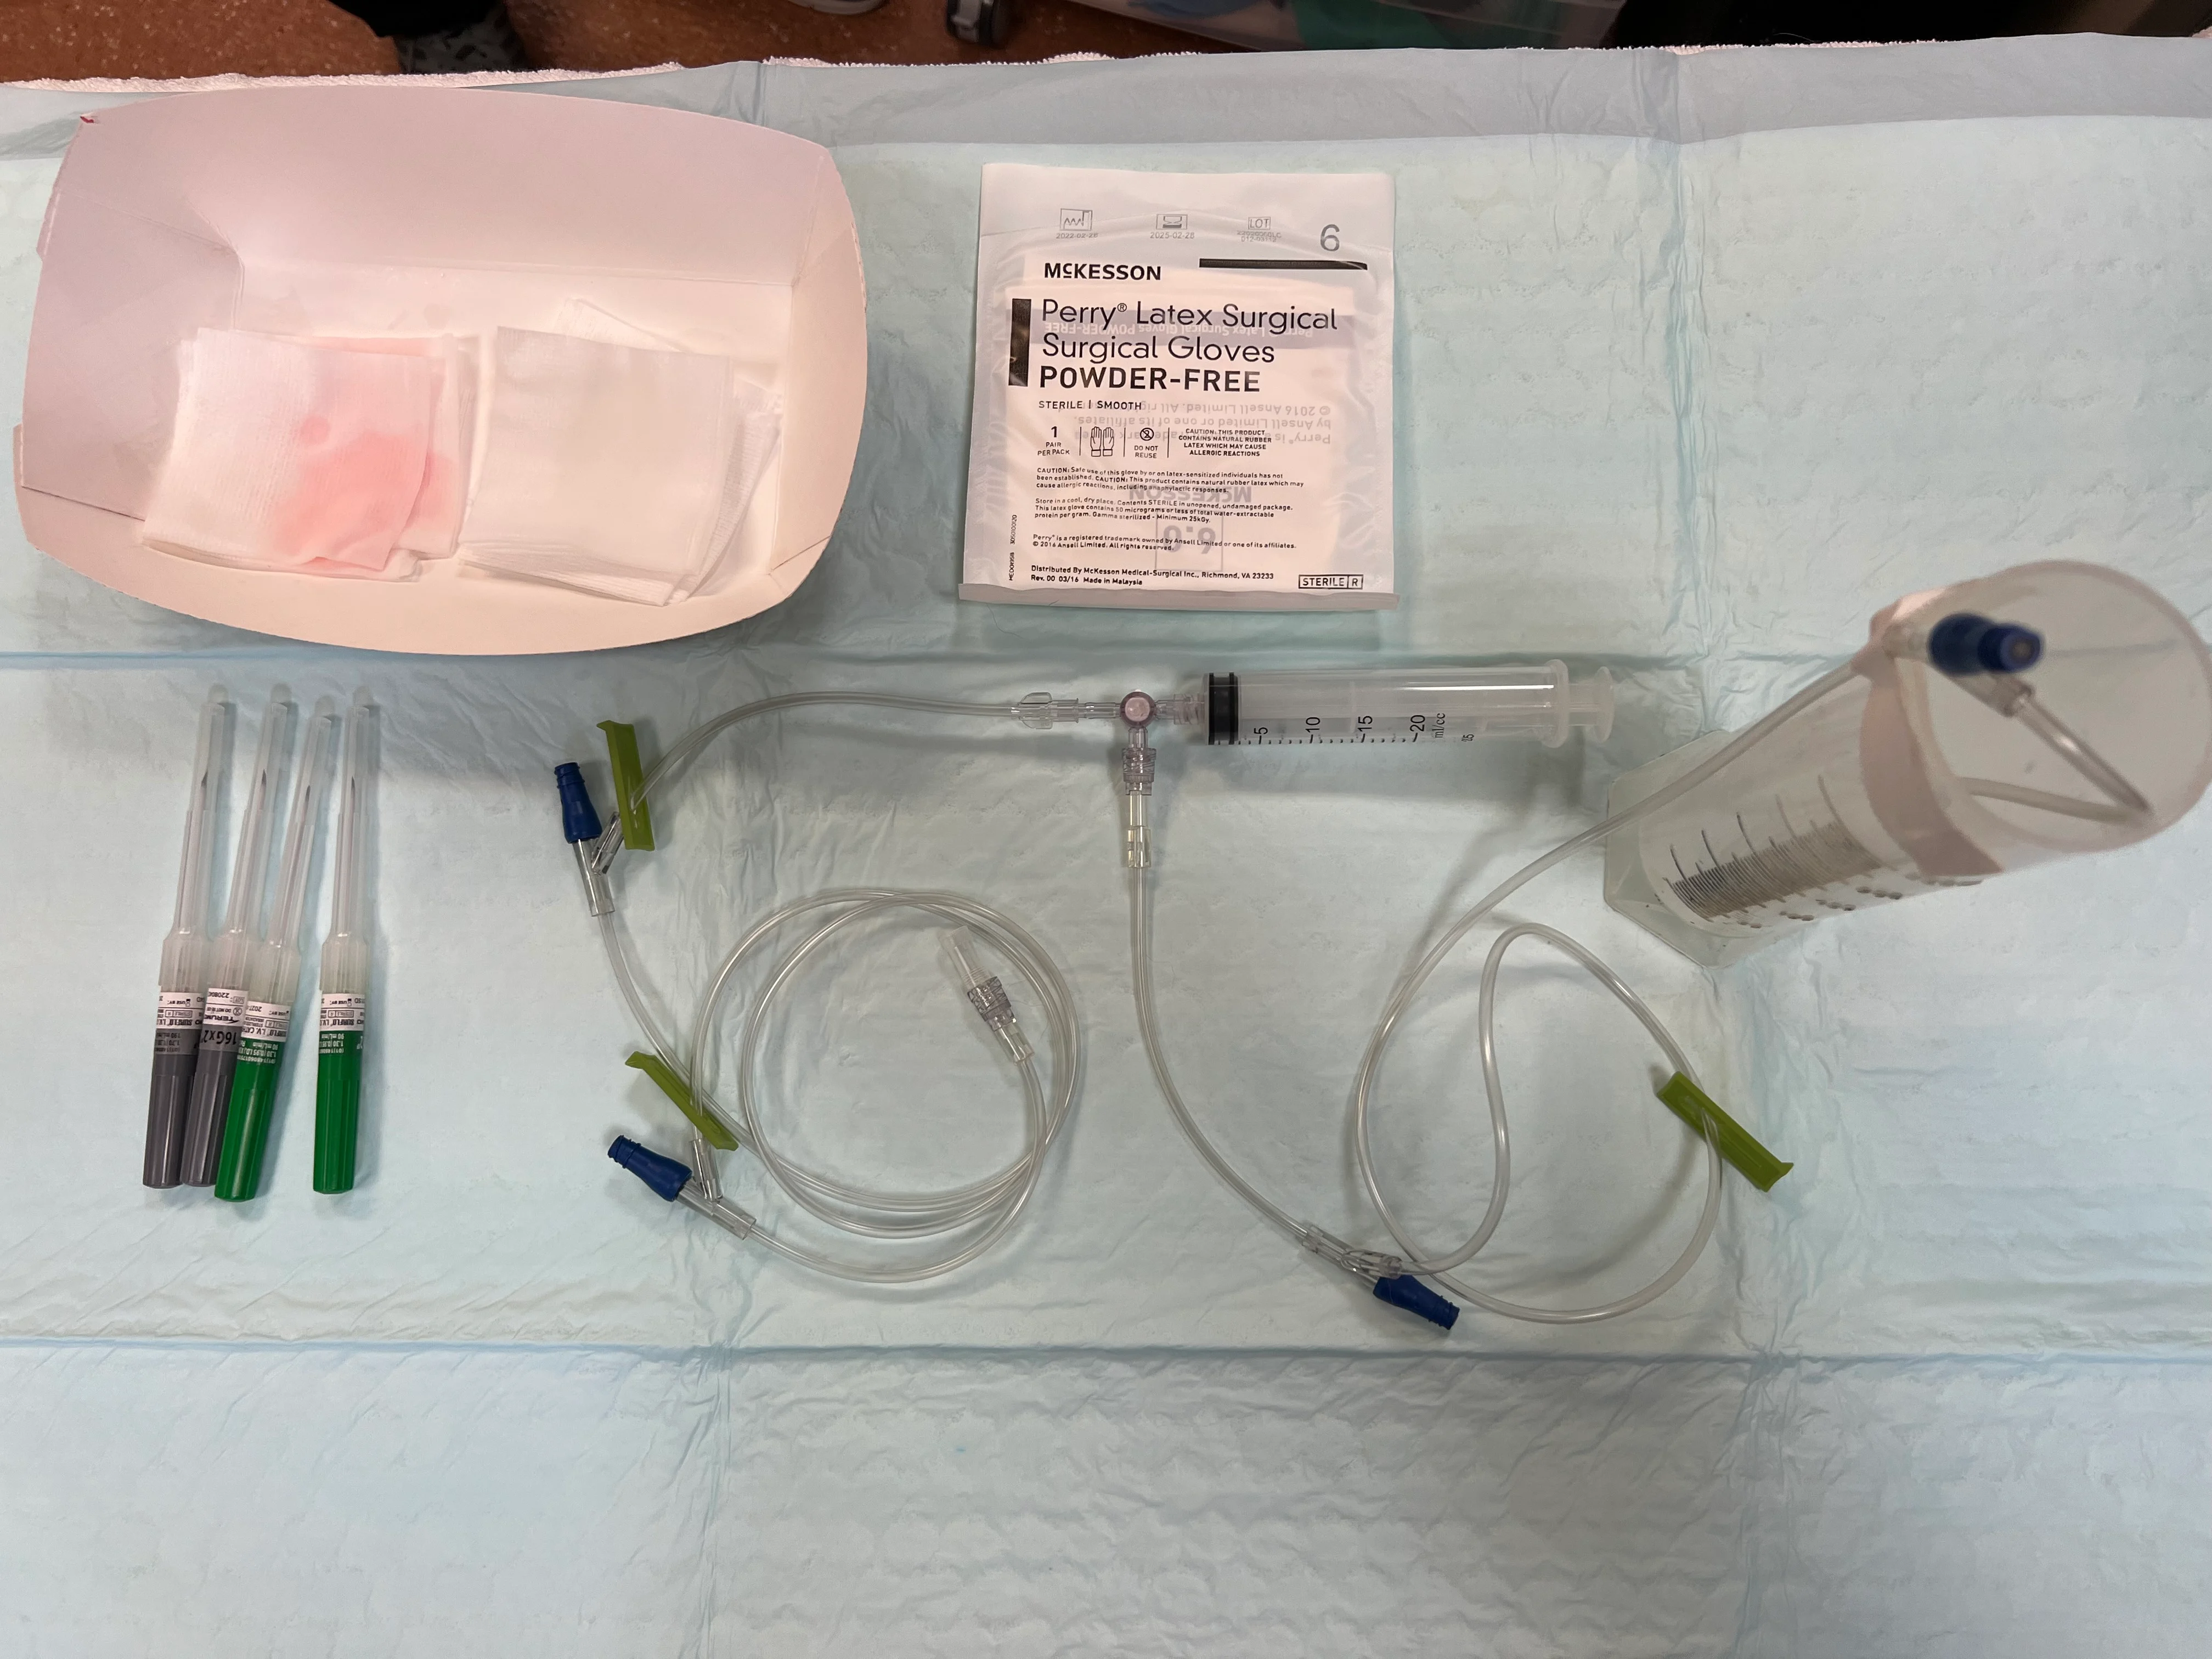

Clippers

Sterile surgical scrub

Gloves

Hypodermic needle (cats, 22 gauge, 1 inch; dogs, 18-22 gauge, 1-1.5 inch based on patient size), over-the-needle catheter (cats, 22 gauge; dogs, 18-22 gauge), or butterfly catheter (cats or small dogs, 23 gauge)

2 extension sets

3-way stopcock

Collection container

Syringes (6-60 mL based on amount and viscosity of fluid expected, size of needle/catheter, and operator preference)

Lavender-top and nonadditive tubes

ECG (if available)

Ultrasound (if available)

Sedation (optional)

Oxygen (optional)

Step 1: Prepare Collection Equipment

Using sterile technique, connect the 3-way stopcock to a syringe and 2 extension sets, with one set connected to the needle and the other taped inside the collection container. Ensure the stopcock is turned off to the patient.